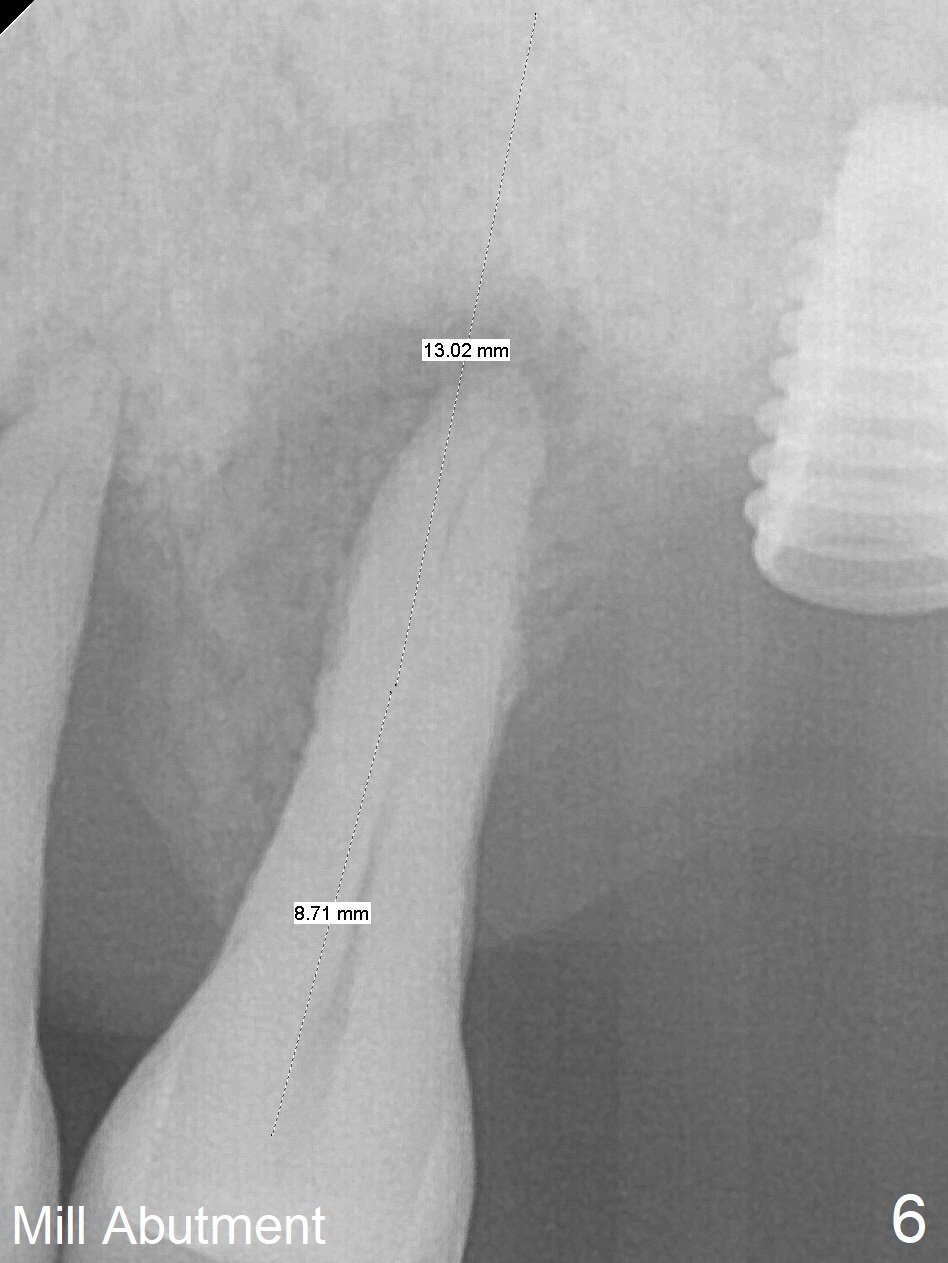

Bone height at #14 two months post exfoliation is ~ 4 mm (Fig.1). Bone expansion is difficult because of dense bone. After drilling, a 4.5 mm tap is inserted with stability (Fig.2). Sinus lift is accomplished with RT3 and autogenous bone prior to placement of a 4.5x8.5 mm implant (Fig.3). Because of flapless surgery and tight and long gingiva, bone graft around the coronal end of the implant is intentionally not placed. A 5.5x5(4) mm abutment is immediately placed for an immediate provisional. (Fig.4). Take PA and impression when the patient returns. The provisional dislodges 3.5 months postop (Fig.4); impression is taken. The patient reports hot sensitivity and pain after meal at the implant site (Fig.5). After removal of the implant crown/abutment, she feels better. If not, it seems necessary to extract the tooth #13 for a 13 mm long implant with a mill abutment (Fig.6).